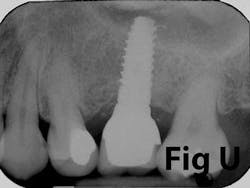

There is an abundance of literature showing increased gingival inflammation around natural dentition (exacerbated when a fixed restoration is present) when there is less than 2 mm AG. (Figs. 8, 9: post grafting) There is an abundance of literature showing increased incidence of peri-implant mucositis when there is inadequate attached tissue — a weaker connective tissue adhesion and lack of Sharpey’s fibers make the peri-implant tissue even more susceptible to bacterial challenge. (1-6, 8, 10) And as periodontitis is always preceded by gingivitis, peri-implantitis will be preceded by peri-implant mucositis. If we can decrease the incidence of peri-implant mucositis by providing a better and more resilient tissue phenotype, we can lower the incidence of peri-implantitis.The FGG procedure is indicated in cases of implant therapy where this is less than 2 mm of attached tissue present. Sometimes, a FGG is preferred over CTG because: (1) the FGG results in greater gain of attached tissue, (2) the FGG alleviates frenum/muscular pull whereas the connective tissue may increase muscular tension after the flap is coronally advanced, and (3) creeping attachment is often a positive byproduct of the FGG procedure.

Case No. 1